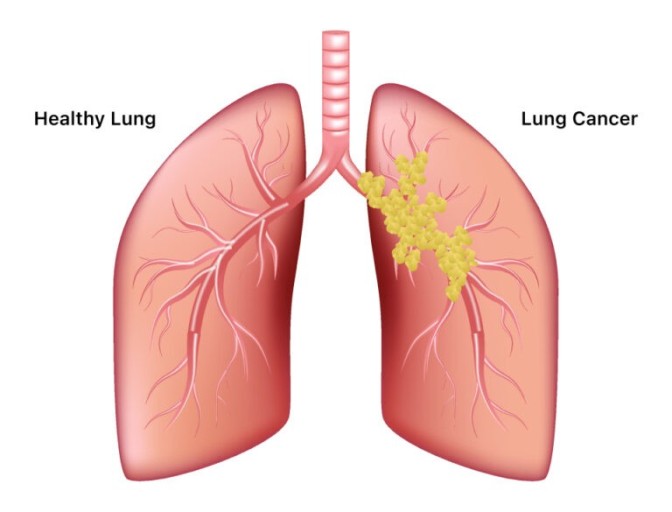

폐렴 증상 폐렴은 폐의 세균, 바이러스, 곰팡이 등 감염으로 인해

폐포(폐 속의 공기 주머니)에 염증이 생기고, 고름이나 액체가 차는 질환입니다.